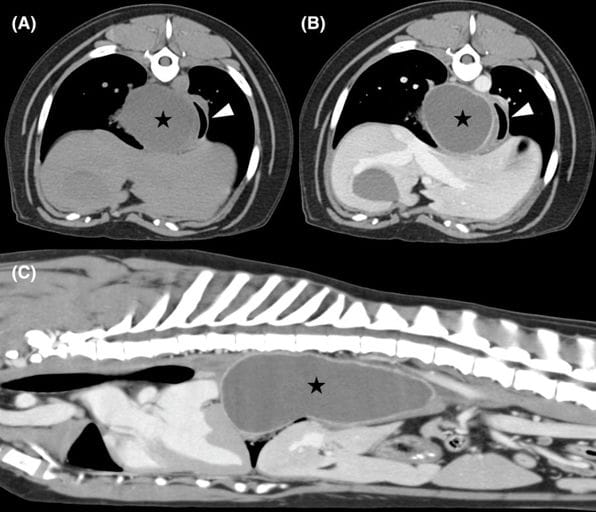

Transverse (A) precontrast and (B) post-contrast, and (C) sagittal post-contrast reformats displayed in a soft tissue algorithm of Case 2 showing the large caudal mediastinal paraesophageal abscess (black star). The white arrowhead points to the esophagus. The transverse images are displayed with the patient's left side on the right side of the image.

Both dogs had large, thick-walled paraesophageal abscesses protruding through the esophageal hiatus and causing mass effect on adjacent structures. No foreign material was identified on CT, esophagoscopy (when performed), or intraoperative inspection. Cultures were negative in both cases, and histopathology demonstrated chronic suppurative or neutrophilic inflammation without identifiable pathogens. Surgical debridement and lavage were completed successfully, with only minor complications noted (hemorrhage requiring vessel sealing, mild hypoxia during recovery, transient hypoglycemia). Both dogs recovered uneventfully, were discharged within 3–4 days, and showed no recurrence at 7-month telephone follow-up. Repeat imaging in one dog showed only mild residual soft-tissue opacity without evidence of abscess recurrence.